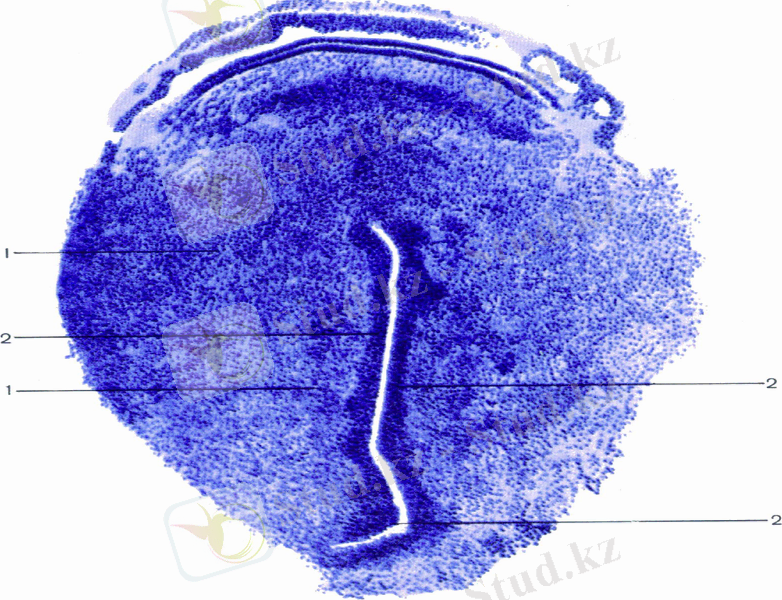

4. Бөлшектену

ПРОГЕНЕЗ